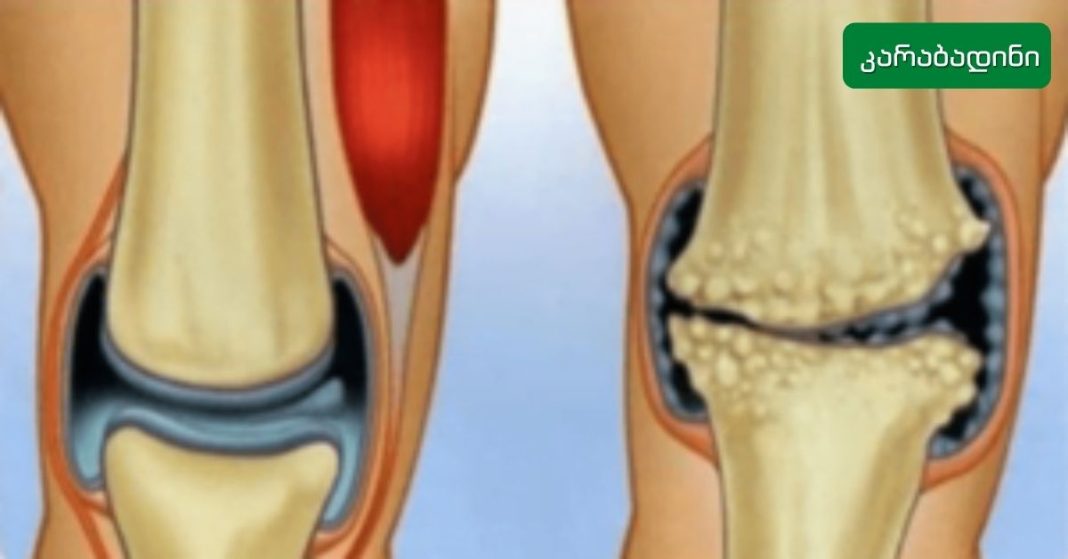

Knee pain can stem from various causes, and it’s a common issue many people face. Some of the most frequent causes include physical trauma, overexertion, sudden injuries, or conditions like arthritis. Regardless of the cause, the most typical symptoms are pain, swelling, and stiffness.